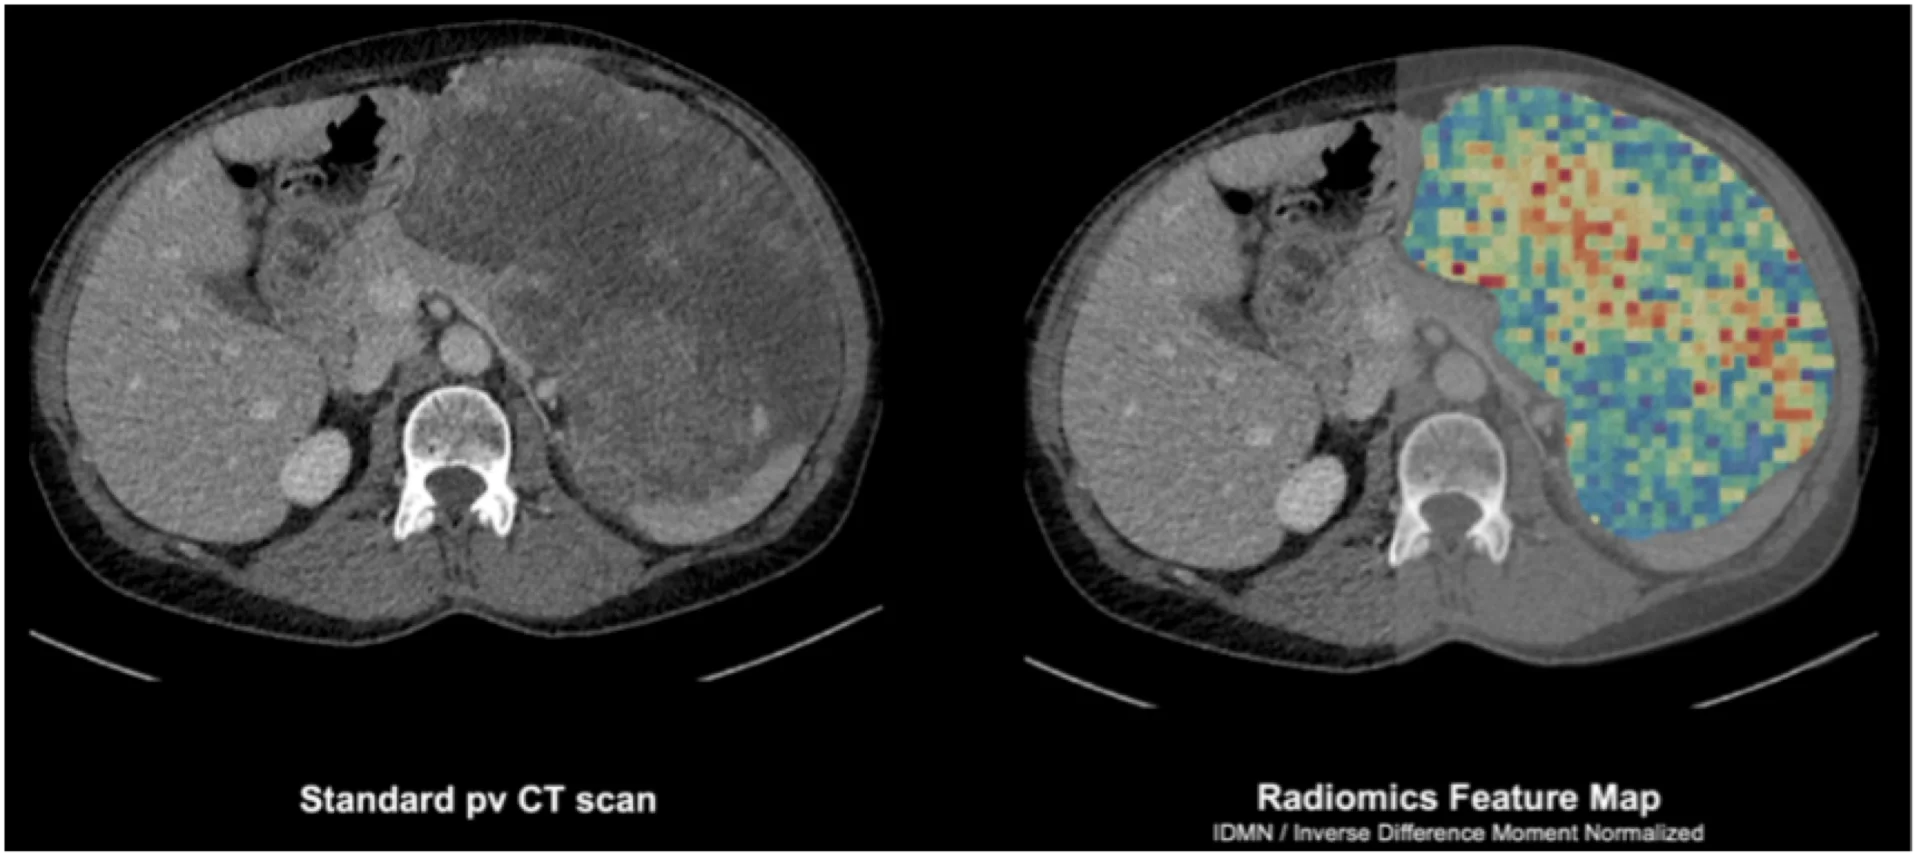

Mit der Analyse der Signalverteilung der Pixel durch Radiomics kann der hohe Kontrast des Photon-Counting-CTs optimal genutzt werden. Welche Chancen bietet Radiomics und wie unterscheidet es sich von bisherigen Bildinformationen, insbesondere am Photon-Counting-CT?

Radiomics ermöglicht die Extraktion quantitativer Bildmerkmale, die über das hinausgehen, was das menschliche Auge wahrnehmen kann. Diese Merkmale umfassen Textur-, Dichte- und Formanalysen, die für eine präzisere Klassifikation von Tumoren genutzt werden. In Kombination mit künstlicher Intelligenz (KI) lassen sich so subtile Muster erkennen, die eine präzisere Diagnosestellung und Therapieplanung ermöglichen.

Gerade in der onkologischen Bildgebung ist die Heterogenität von Tumorerkrankungen für die Biopsieplanung und die Therapie eine große Herausforderung. Die Informationen, die man mittels künstlicher Intelligenz und Radiomics aus den Bilddaten gewinnen kann, ermöglichen uns nun erstmalig, die sogenannte tumorale Heterogenität im Bild darzustellen und so neuartige vielversprechende Therapiekonzepte für unsere Patientinnen und Patienten zu entwickeln. Hier hilft uns auch das bessere Signal beim Photon-Counting-CT. Die quantitativen Features haben eine gewisse Anfälligkeit für das Bildrauschen. Im Photon-Counting-CT messen die Detektoren einzelne Photonen und reduzieren so das Bildrauschen dramatisch. Das elektronische Rauschen kann durch das Messen von einzelnen Photonensignalen abgetrennt und aus dem gesamten Datensatz entfernt werden. Somit hat man zum einen eine bessere Dosiseffizienz und eine bessere Bildqualität, zum anderen eine viel höhere Stabilität. Zudem ermöglicht der spektrale Kontrast die Anwendung von virtuell monoenergetischen Rekonstruktionen, wodurch die Vergleichbarkeit von Bilddaten – etwa für Forschungszwecke oder das KI-Training – optimiert wird.